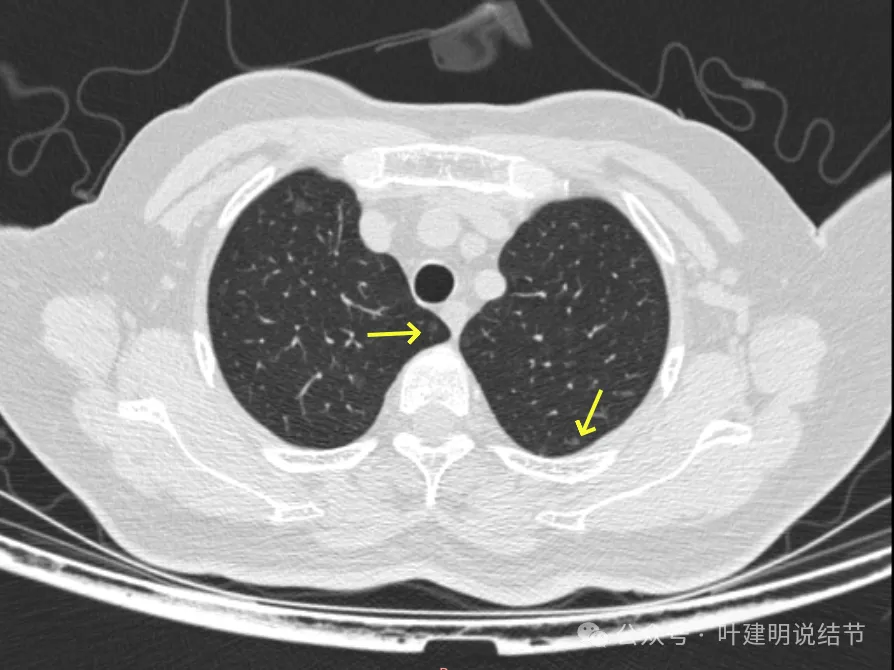

病灶10:右侧胸膜下淡磨玻璃结节,轮廓较清。

病灶19-20:两肺淡磨玻璃结节,轮廓较清,小但边界清楚。